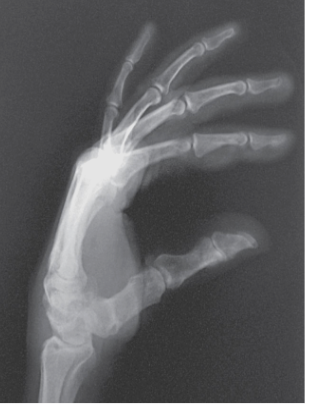

What should the part position be like for a fan lateral hand image?

A

forearm on table with elbow flexed 90 degrees and hand resting on medial surface

part position - what should happen to the palm of the hand and the radial and ulnar styloid processes when the hand is in a fan lateral position?

the ulnar and radial styloid processes should be superimposed and perpendicular to IR

the palm of the hand should be perpendicular to the IR

Where should the central ray enter for a fan lateral hand?

perpendicular to the second MCP point

what are the structures shown in a fan lateral position?

anatomy from fingertips to distal radius and ulna

eval - what should happen to the distal radius and ulna in a fan lateral hand position?

they should be superimposed